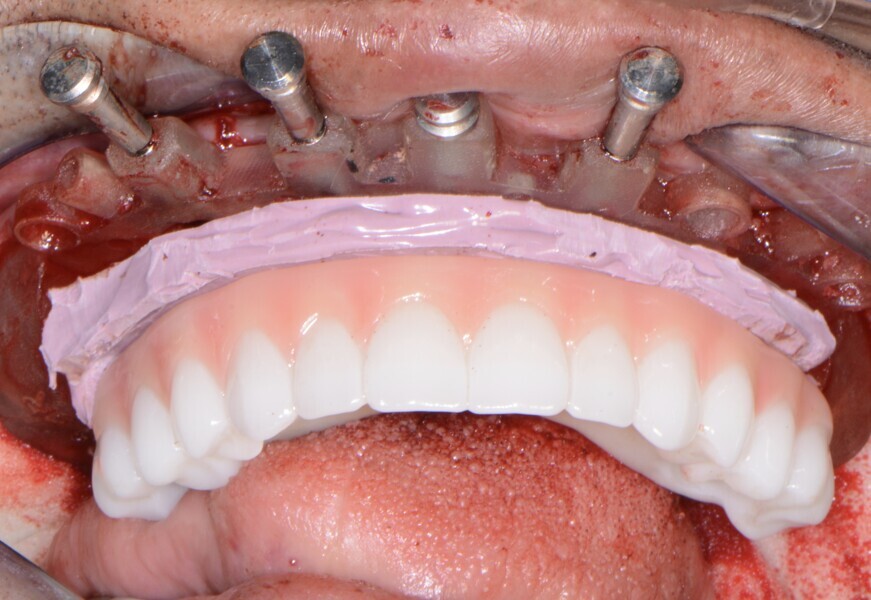

Fig. 15: Insertion of provisional restoration.